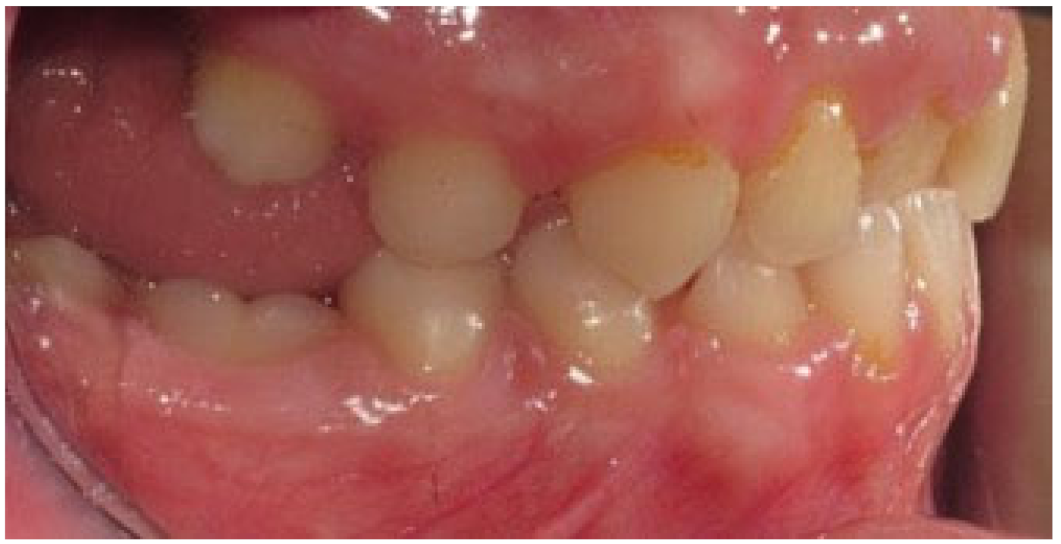

The phenomenon where molars cease to erupt before they emerge, without a physical barrier in the eruption path or as a consequence of an atypical location, is defined as primary retention. The alveolar support of a primarily retained molar, which does not resorb occlusally, is considered a normal barrier to the eruption path. Primary retention is similar to “unerupted” and “embedded” teeth [9]. In the event that the eruption of a permanent tooth is at least 2 years delayed compared to what is normally expected, primary retention should be a clinical entity to take into account. A radiographical follow-up of a minimum of 6 months is suggested as an initial control to determine whether the tooth is showing any eruptive movement or not [10]. The suggested radiographic methods include a periapical or even panoramic X-ray. Primary retention is the possible result of a disturbance in the dental follicle that does not succeed in initiating the metabolic events responsible for bone resorption in the eruption traject [11] (Figure 1 and Figure 2).

Figure 1.

Patient presenting eruption failure of the upper left second molar due to primary retention.

Figure 2.